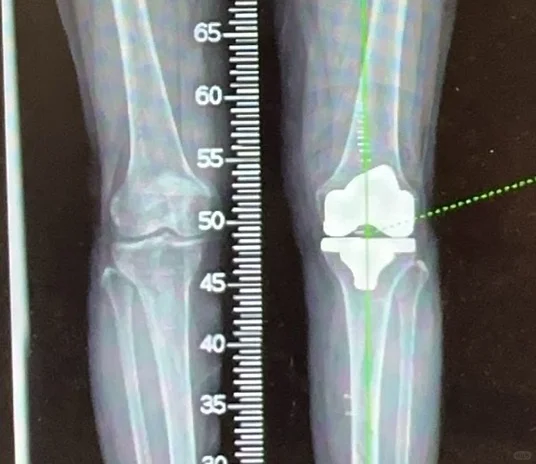

关节置换

髋膝关节置换手术是二十世纪以来最成熟的手术,1小时的手术时间能够给患者带来关节的重生,从此告别让人无法忍受的疼痛,回归正常生活,老人上下楼梯爬山跳舞不是梦。

给大家看看我们的手术器械和术后影像,抡大锤的马医生在线回复您的疑问,点个关注,持续解答。